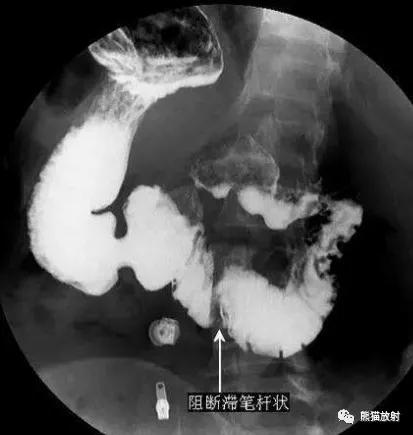

X线表现:

①十二指肠梗阻性表现:钡剂通过十二肠升段受阻,其上扩张。轻者仅为十二指肠舒张,蠕动活跃亢进,逆蠕动多次发生;严重者十二指肠明显扩张,蠕动及逆蠕动频繁,钡剂可反流入胃,甚至出现胃扩张。

②十二指肠升段笔杆状压迹:这一征象并非常见。表现为升段有光滑整齐的纵行压迹,状如“笔杆”,黏膜纹变平。

③体位改变的影响:十二指肠梗阻、淤张现象,常于立位、仰卧位时显著,而于俯卧位、胸膝卧位或向上推压小肠时缓解或消失。